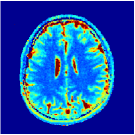

Two sets of experiments were conducted here: first, we used the 2D and 3D acquisition sequences for scanning a healthy volunteer’s brain (real-world acquisitions). Figures 6 and 7 display the parametric maps reconstructed from 2D spiral and radial readouts. We computed the T1, T2 and proton density (PD) maps using baseline reconstruction algorithms ZF, VS, LR, FLOR, AIR-MRF and our proposed LRTV. While baselines use DM either for quantitative inference or also during reconstruction (i.e. AIR-MRF), we further compare the DM-free LRTV’s performance when cascaded to DM, KM and MRFResnet for quantitative inference. For the 3D spiral acquisitions we compared LRTV and its closest competitor VS in Figure 8. Outcomes from other tested algorithm are displayed in the supplementary materials (Figure S5). Since FLOR does not use dimensionality-reduction, our system ran out of memory during 3D reconstruction; hence results are not reported in this case.

The LRTV-DM and LRTV-MRFResnet perform on par, and both outperform all tested baselines for reconstructing T1, T2 and PD maps in all acquisition schemes. This can be observed both visually in Figures 6, 7, 8, S2 and S3, and quantitatively in Table IV across all tested metrics. Other baselines were unable to successfully remove the under-sampling artefacts in TSMIs, and these errors propagated to the parameter inference phase and resulted in inaccurate maps. Temporal-only priors incorporated within LR are shown insufficient to regularise the inverse problem and LR sometimes (e.g. 2D spiral acquisitions) can admit solutions with even stronger artefacts than the model-free ZF baseline. This issue was previously studied for other non-Cartesian MRF readouts that similar to our spiral/radial trajectories, miss to sample the corners of the k-space in all timeframes (see section 2.2.2 and figure 2 in [19]). In the absence of reference for the k-space corners information, the LR iterations despite minimising the objective can converge to solutions with high-frequency artefacts, as visible in the computed maps. This highlights the need for adding an appropriate spatial-domain regularisation. FLOR reduces the LR’s artefacts but this improvement is limited because the suggested nuclear norm penalty does not incorporate an explicit spatial regularisation. Further for reducing artefacts, FLOR can introduce an undesirable bias in the computed T1/T2 maps e.g. see error maps in Figures S2 and S3. The non model-based VS baseline incorporates spatial regularisation and results in spatially smoother maps than ZF and LR, but it is unable to output artefact-free images. Further and consistent with our in-vitro experiment, we observe that VS overestimates the T2 values (e.g. in White and Grey matter regions) in tested 2D acquisitions i.e. the spatial regularisation trades off agains the quantification accuracy. The model-based AIR-MRF adds spatial regularisation through 2D/3D low-pass Gaussian filters however this trades off the sharpness of the computed maps and can increase the errors at the tissue boundaries (we searched Gaussian spreads that keep the blurs and high-frequency artefacts minimal). For our acquisition readouts, Gaussian filters performed better than disk filters of [19] for avoiding strong Gibbs artefacts. On the other hand, the spatiotemporally regularised LRTV greatly improves the TSMI reconstructions i.e. 4 dB enhancement compared to the closest competitor baseline (Table IV). This enables computing accurate and aliased-free multi-parametric inference using DM or the DM-free learning-based alternative MRFResnet as visible in Figures 6, 7, 8, S2 and S3. MRResnet and DM score competitive quantitative inference results i.e. T1 and T2 MAPE less than 5% and 9%, respectively (Table IV). KM also outputs comparably accurate T1 maps, however this shallow learning model despite having a model size larger than MRFResnet, is unable to learn accurate T2/PD quantification and it results in poor estimated maps, consistent with our observations in section VI-C.